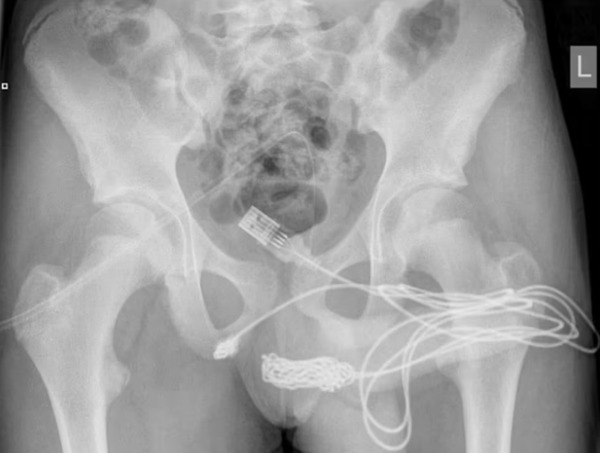

(少年の体に入っていたUSBケーブル↓)

イギリスの15歳の少年はUSBケーブルを使って、自らのモノの長さを測定しようと思いついたそうです。そして少年はUSBケーブルを自分の先っちょから挿入していったのですが、調子に乗ってぶち込み過ぎて抜けなくなってしまったとのこと。

どうやらUSBケーブルが体内でもつれたり引っ掛ってしまったようです。

少年は必死で抜こうと試みたものの出血までするようになり、どうしようもなくなり母親に連れられて病院を訪れたそうです。

しかし医療チームが挑戦しても簡単に抜くことは出来そうもない状態で、結局手術で取り除くことになってしまったとのこと。

最終的にケーブルは外尿道口から引き抜かれ、少年はその順調に回復して無事退院したそうです。